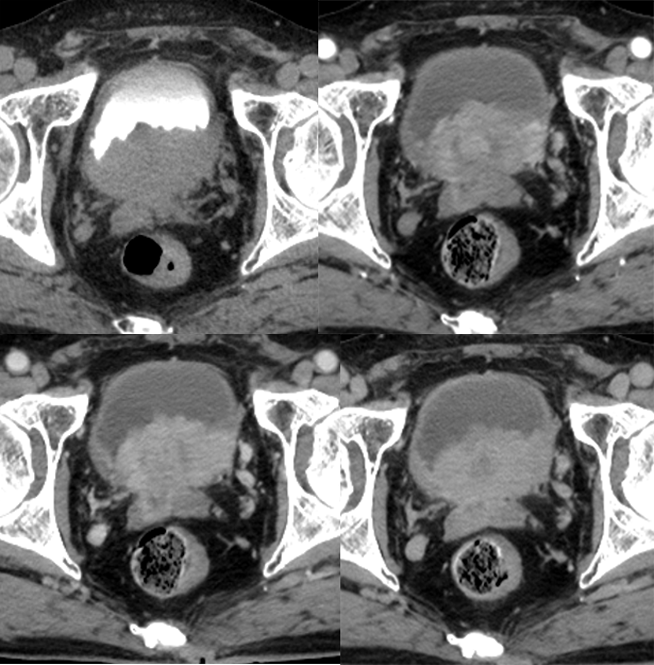

2)膀胱癌:是泌尿系统最常见的恶性肿瘤之一,多为移行上皮癌,好发于成年男性,影像学表现:好发于后侧壁及三角区,囊壁局限或弥漫型增厚、腔内肿块,易囊变坏死,与膀胱壁分界不清,增强扫描明显强化,可侵犯浆膜面,盆腔淋巴结肿大。

膀胱癌,累及前列腺及精囊腺

神经源性膀胱,壁弥漫性增厚,伴巨大憩室形成

神经源性膀胱,壁弥漫性增厚,过度充盈